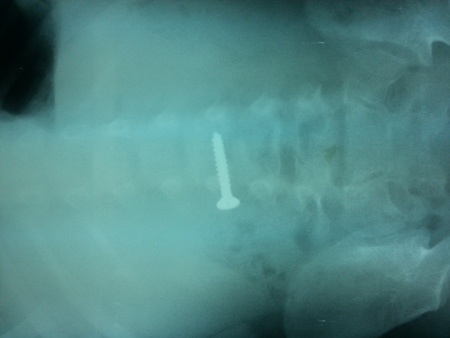

(Dân trí) - Chiều 15/7, các bác sĩ Bệnh viện Hữu nghị Việt Nam - Cu Ba Đồng Hới cho biết, bệnh viện này vừa tiếp nhận và cấp cứu bé trai V.K.T.D., (3 tuổi, ở xã Lộc Ninh, TP Đồng Hới, tỉnh Quảng Bình) do nuốt 1 chiếc đinh vít vào bụng.

Qua thăm khám và chụp phim Xquang, các bác sĩ phát hiện một chiếc đinh vít xoắn dài khoảng 3cm nằm trong ổ bụng cháu bé.

Chiếc đinh vít dài khoảng 3cm trong bụng bé D

Tuy nhiên, rất may mắn cho cháu D là chiếc đinh vít vào thực quản rồi trôi xuống ruột nên không nguy hiểm tính mạng, không phải phẫu thuật mà chỉ cần theo dõi đinh vít ra ngoài theo đường tiêu hóa.